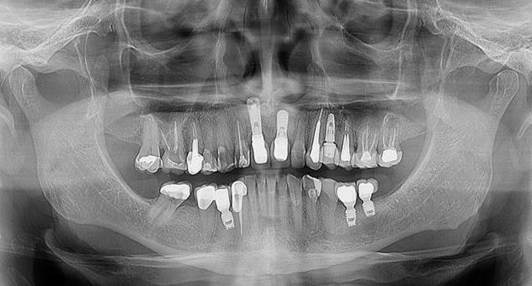

Paciente A. R. S, gênero feminino, 67 anos de idade, compareceu ao consultório particular, em 2020, com a queixa de mobilidade na região dos implantes inferiores. Na anamnese, paciente realizava acompanhamento médico devido ao quadro de diabetes mellitus, com uso de medicamentos específicos. Ao exame clínico, verificado mobilidade acentuada na regão do 36, 37, 46 e 47. Foram solicitados radiografia panorâmica (Figura 04. A) e tomografia computadorizada da área, evidenciando comprometimento periodontal avançado nas reabilitações com implantes dentários. O plano de tratamento proposto foi a remoção dos implantes e nova reabilitação da região atrófica.

Inicialmente, o procedimento cirúrgico consistiu pela remoção dos implantes dentários (Figura 04. B), realização de enxerto imediato (Bio-Oss, Geistlinch, Wolhusen – Suíça), através da técnica de reconstrução tipo tenda, e uso da membrana de colágeno (Bio-Gide, Geistlinch, Wolhusen – Suíça). O Quadro 1 apresenta as principais medidas para avaliação do posicionamento do implante. Após 6 meses, foram instalados dois implantes dentários extra curtos ARCSYS (FGM, Joinvile – SC, Brasil) 4,0 mm x 6,0 mm x 5,0 mm do lado direito e dois implantes na região esquerda 5,0 mm x 5,0 mm. As figuras 05 e 06 evidenciam aspecto radiográfico após a etapa inicial. As recomendações pós-operatórias e a prescrição medicamentosa foram realizadas, resultando em ausência de complicações após a intervenção. O acompanhamento foi feito durante 5 anos, com resultado satisfatório (Figura 7. A – E).

Figura 04. A) Radiografia panorâmica inicial. B) Implantes dentários removidos – região do 36, 37, 46 e 47.

Figura 05. Exames de imagem da região inferior direita. A) Vista panorâmica. B) Reconstruções tridimensionais. C) Cortes transversais oblíquos.

Figura 06. Exames de imagem da região inferior esquerda. A) Vista panorâmica. B) Reconstruções tridimensionais. C) Cortes transversais oblíquos.

Figura 07. A – D) Aspecto final. E) Radiografia panorâmica final.